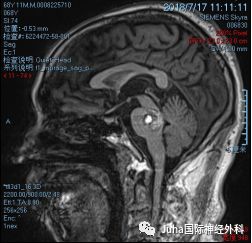

患者:男,67岁,因“左侧肢体乏力麻木、伸舌左偏,口角左歪18天”门诊以“脑干海绵状血管瘤”收入院。

右侧桥脑海绵状血管瘤

MRI显示:脑干海绵状血管瘤主要位于桥脑右侧后方